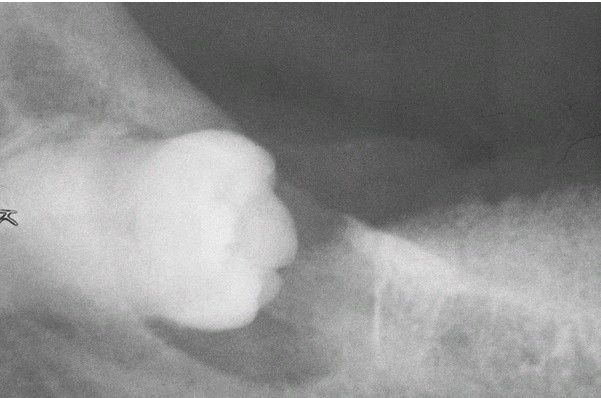

Carcinoma Arising in a Dentigerous Cyst.

Radiolucent lesion surrounding the crown of an impacted third molar in a 56-year-old woman. This was clinically considered to be a dentigerous cyst. (Courtesy of Dr. Richard Ziegler.)